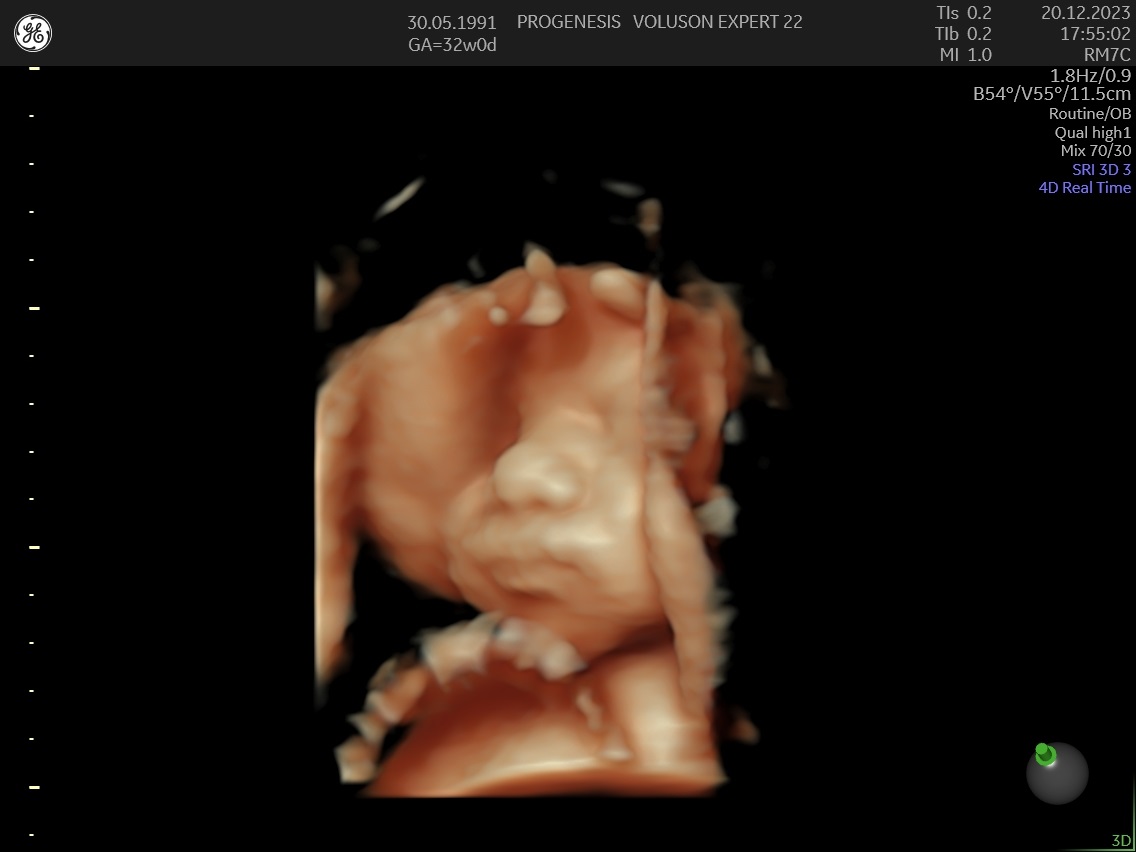

Το 3D/4D LIVE είναι μια νέα τεχνολογία υπερήχων που δημιουργεί εικόνες του εμβρύου σε τρισδιάστατο ή τετραδιάστατο χώρο. Οι εικόνες αυτές είναι πιο ρεαλιστικές από τις παραδοσιακές εικόνες υπερήχων και δίνουν στους γονείς μια πιο ολοκληρωμένη εικόνα του μωρού τους.

Σε πιθανά ανατομικά προβλήματα του εμβρύου μπορούν να βοηθήσουν στην κατανόησή τους από τους γονείς.

Ωστόσο, οι εικόνες 3D/4D LIVE δεν μπορούν να αντικαταστήσουν τις παραδοσιακές εξετάσεις υπερήχων.